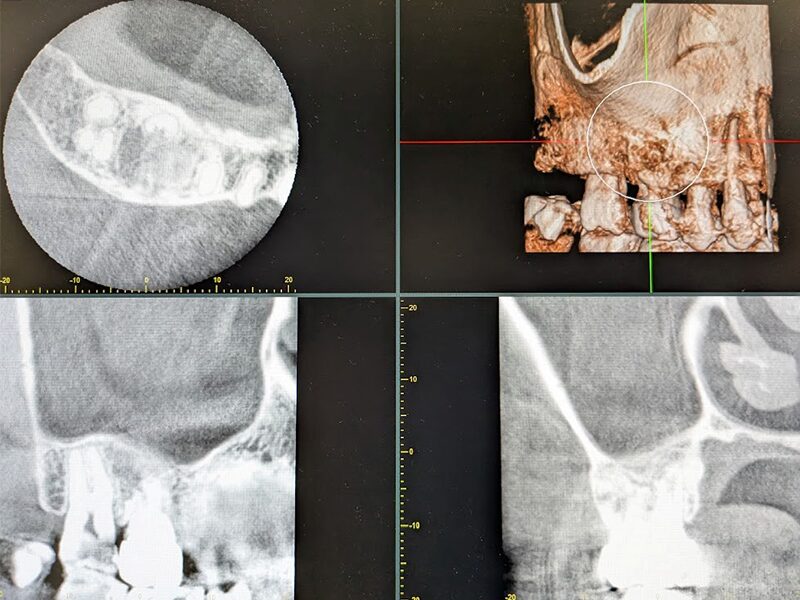

根管治療の再治療になりますが、歯根が弯曲・閉塞しているため根管治療で病巣が治癒せず、上顎洞粘膜の肥厚も残っております。

術後1年半の確認CTです。上顎洞粘膜の肥厚は消失。嚢胞摘出腔に骨が再生してきていることがわかります。再生がなかなか難しいと言われている皮質骨も再生してきております。